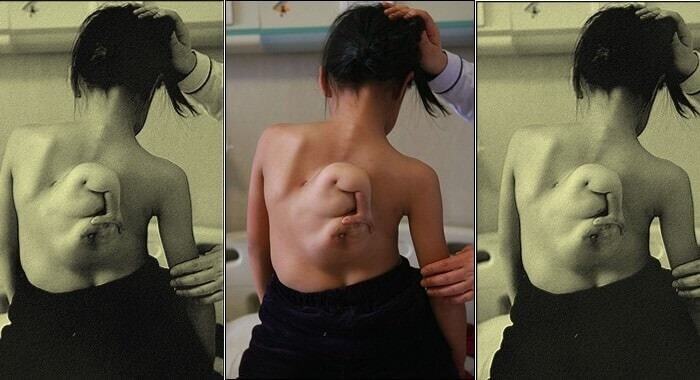

Инь Ксин

Девочка была буквально "заторможена" развитием своего нерожденного близнеца и будет страдать всю оставшуюся жизнь. Когда девочки родились, они сразу заметили маленькие ручки, растущие из их спинок. Со временем расстройство перешло на пальцы рук и ног, затем на живот, а потом на грудь; к 11 годам половина ее спины содержала неразвитый плод. В то время у родителей девочки не было денег на операцию, но в 2007 году паразиты были удалены.